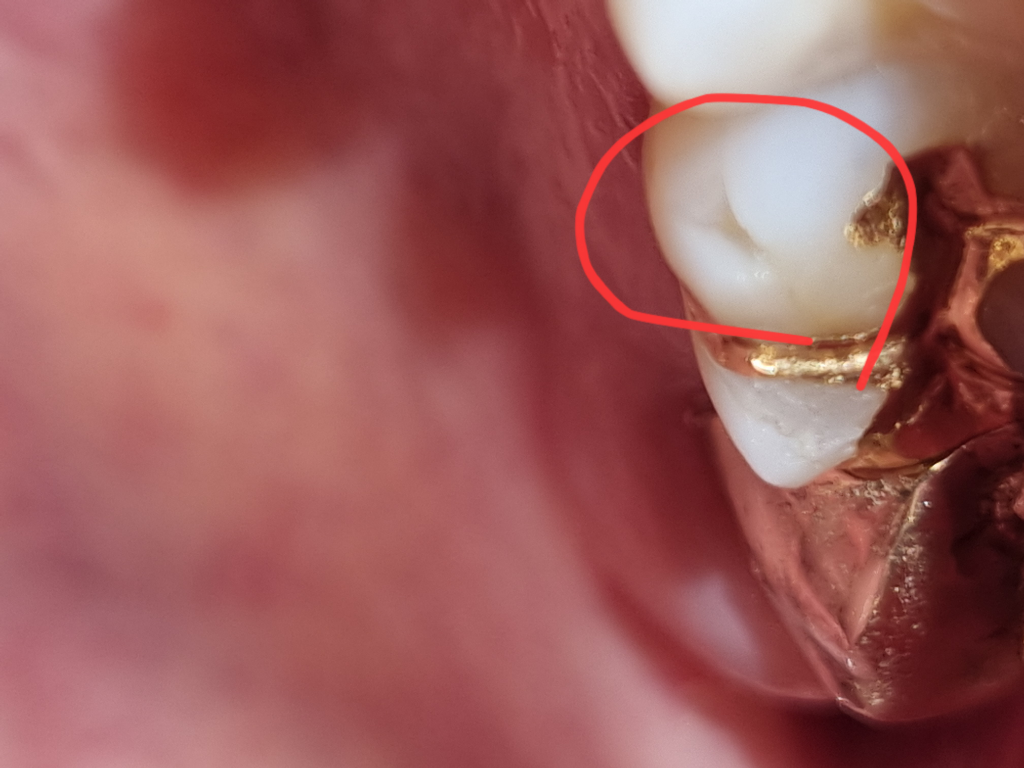

치아 일부분 끝부분만 떨어져 나간 상태입니다, 떨어져 나가 약간 파인 것으로 보이니 이 파인 부분만 떼우고 전체적으로 씌우는

크라운은 하지 않아도 될 것으로 보입니다.

치과 방문 후 검사를 받아보셔야 합니다. 파절된 부위가 생각보다 크고 파절되고 남아 있는 치질에 금이 가 있는 것이 사진으로도 보입니다. 정확한 진단을 받아봐야 하고 금이 어느정도 파급되었는지에 따라 치료 과정이 달라질 것으로 보입니다. 통증이나 불편감이 없더라도 빠른 시일 내에 치과 방문 후 검진을 받아보시길 바랍니다.

사진으로 봤을경우에는 보철물 주변으로 금이 가고 이로 인해서 치아가 파절된것으로 보입니다.

치아에 금이가게 되면 시간이 지나면서 금이 진행될 수 있어요.

치아에 가있는 금이 신경까지 진행이 되면 통증을 유발하는 경우도 있습니다.

때문에 경우에 따라서는 빠른 치료가 필요할수도 있습니다.

금이간 치아는 금이간 부위를 제거하고 씌우는 보철치료를 하는것이 일반적입니다.